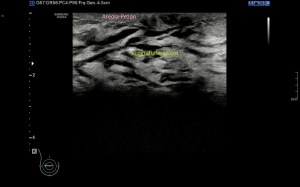

Al explorar la parte interna del muslo, en la zona donde nos señala la paciente encontramos esto…

Rotura

Una imagen de semiología heterogénea que me pareció una rotura fibrilar importante afectando al interior de un músculo de localización interna del que en un primer momento sospeché que podía ser el vasto interno, pero la anatomía no cuadraba, demasiado interno, demasiado cerca de los vasos…

Después de estudiar la rotura en dos planos (imagen 1 y 2) y medirla (imagen 3 y 4), documentarla bien referenciándola con la anatomía locorregional, incluidos los vasos (imagen 5), decidí seguir el recorrido del músculo partiendo desde la rotura siguiendo las instrucciones que me había comentado la paciente y me dí cuenta que el músculo afectado cruzaba el muslo desde el tercio proximal del muslo, en la cara anterior de la cadera (en su porción más superficial) hasta la cara interna de la pierna…en concreto desde la espina iliaca antero superior y terminando en la inserción de la Pata de Ganso.

Como muy bien indicó la propia paciente, el músculo afectado era el sartorio…y es que no hay mejor conocedor del cuerpo que uno mismo…El Sartorio es el músculo el músculo más largo del organismo, pero yo nunca vi una rotura en esta localización, la anatomía confirmó las sospechas, previa consulta de un atlas de anatomía y la correlación con la exploración ecográfica.